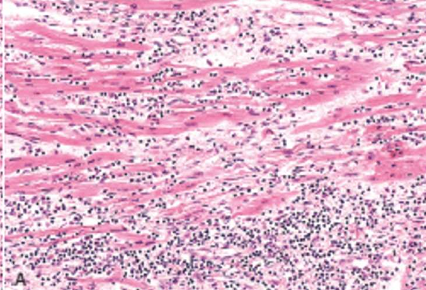

Idiopathic (Fiedler’s) Myocarditis

Diffuse idiopathic myocarditis